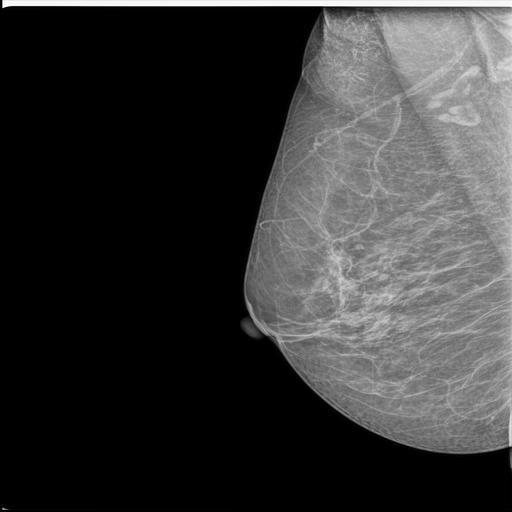

MammoAI revolutionizes breast cancer diagnostics by transforming mammograms into clear, evidence-based reports with actionable next steps. The app addresses critical delays in analysis and limited specialist access, providing faster, clinically informed insights directly from medical imaging and literature.

- Mammogram Upload & Preprocessing – Users can upload images in common medical formats; the app prepares the image for analysis.

- Intelligent Diagnosis & Treatment Reports – Fine-tuned models and LLM-powered agents analyze images and notes, querying specialized medical knowledge bases to generate actionable insights.

- Comprehensive Final Report – Combines mammogram findings, diagnosis, recommended next steps, and practitioner notes into a single, clear report.

Use the following publicly available mammogram images for testing purposes: